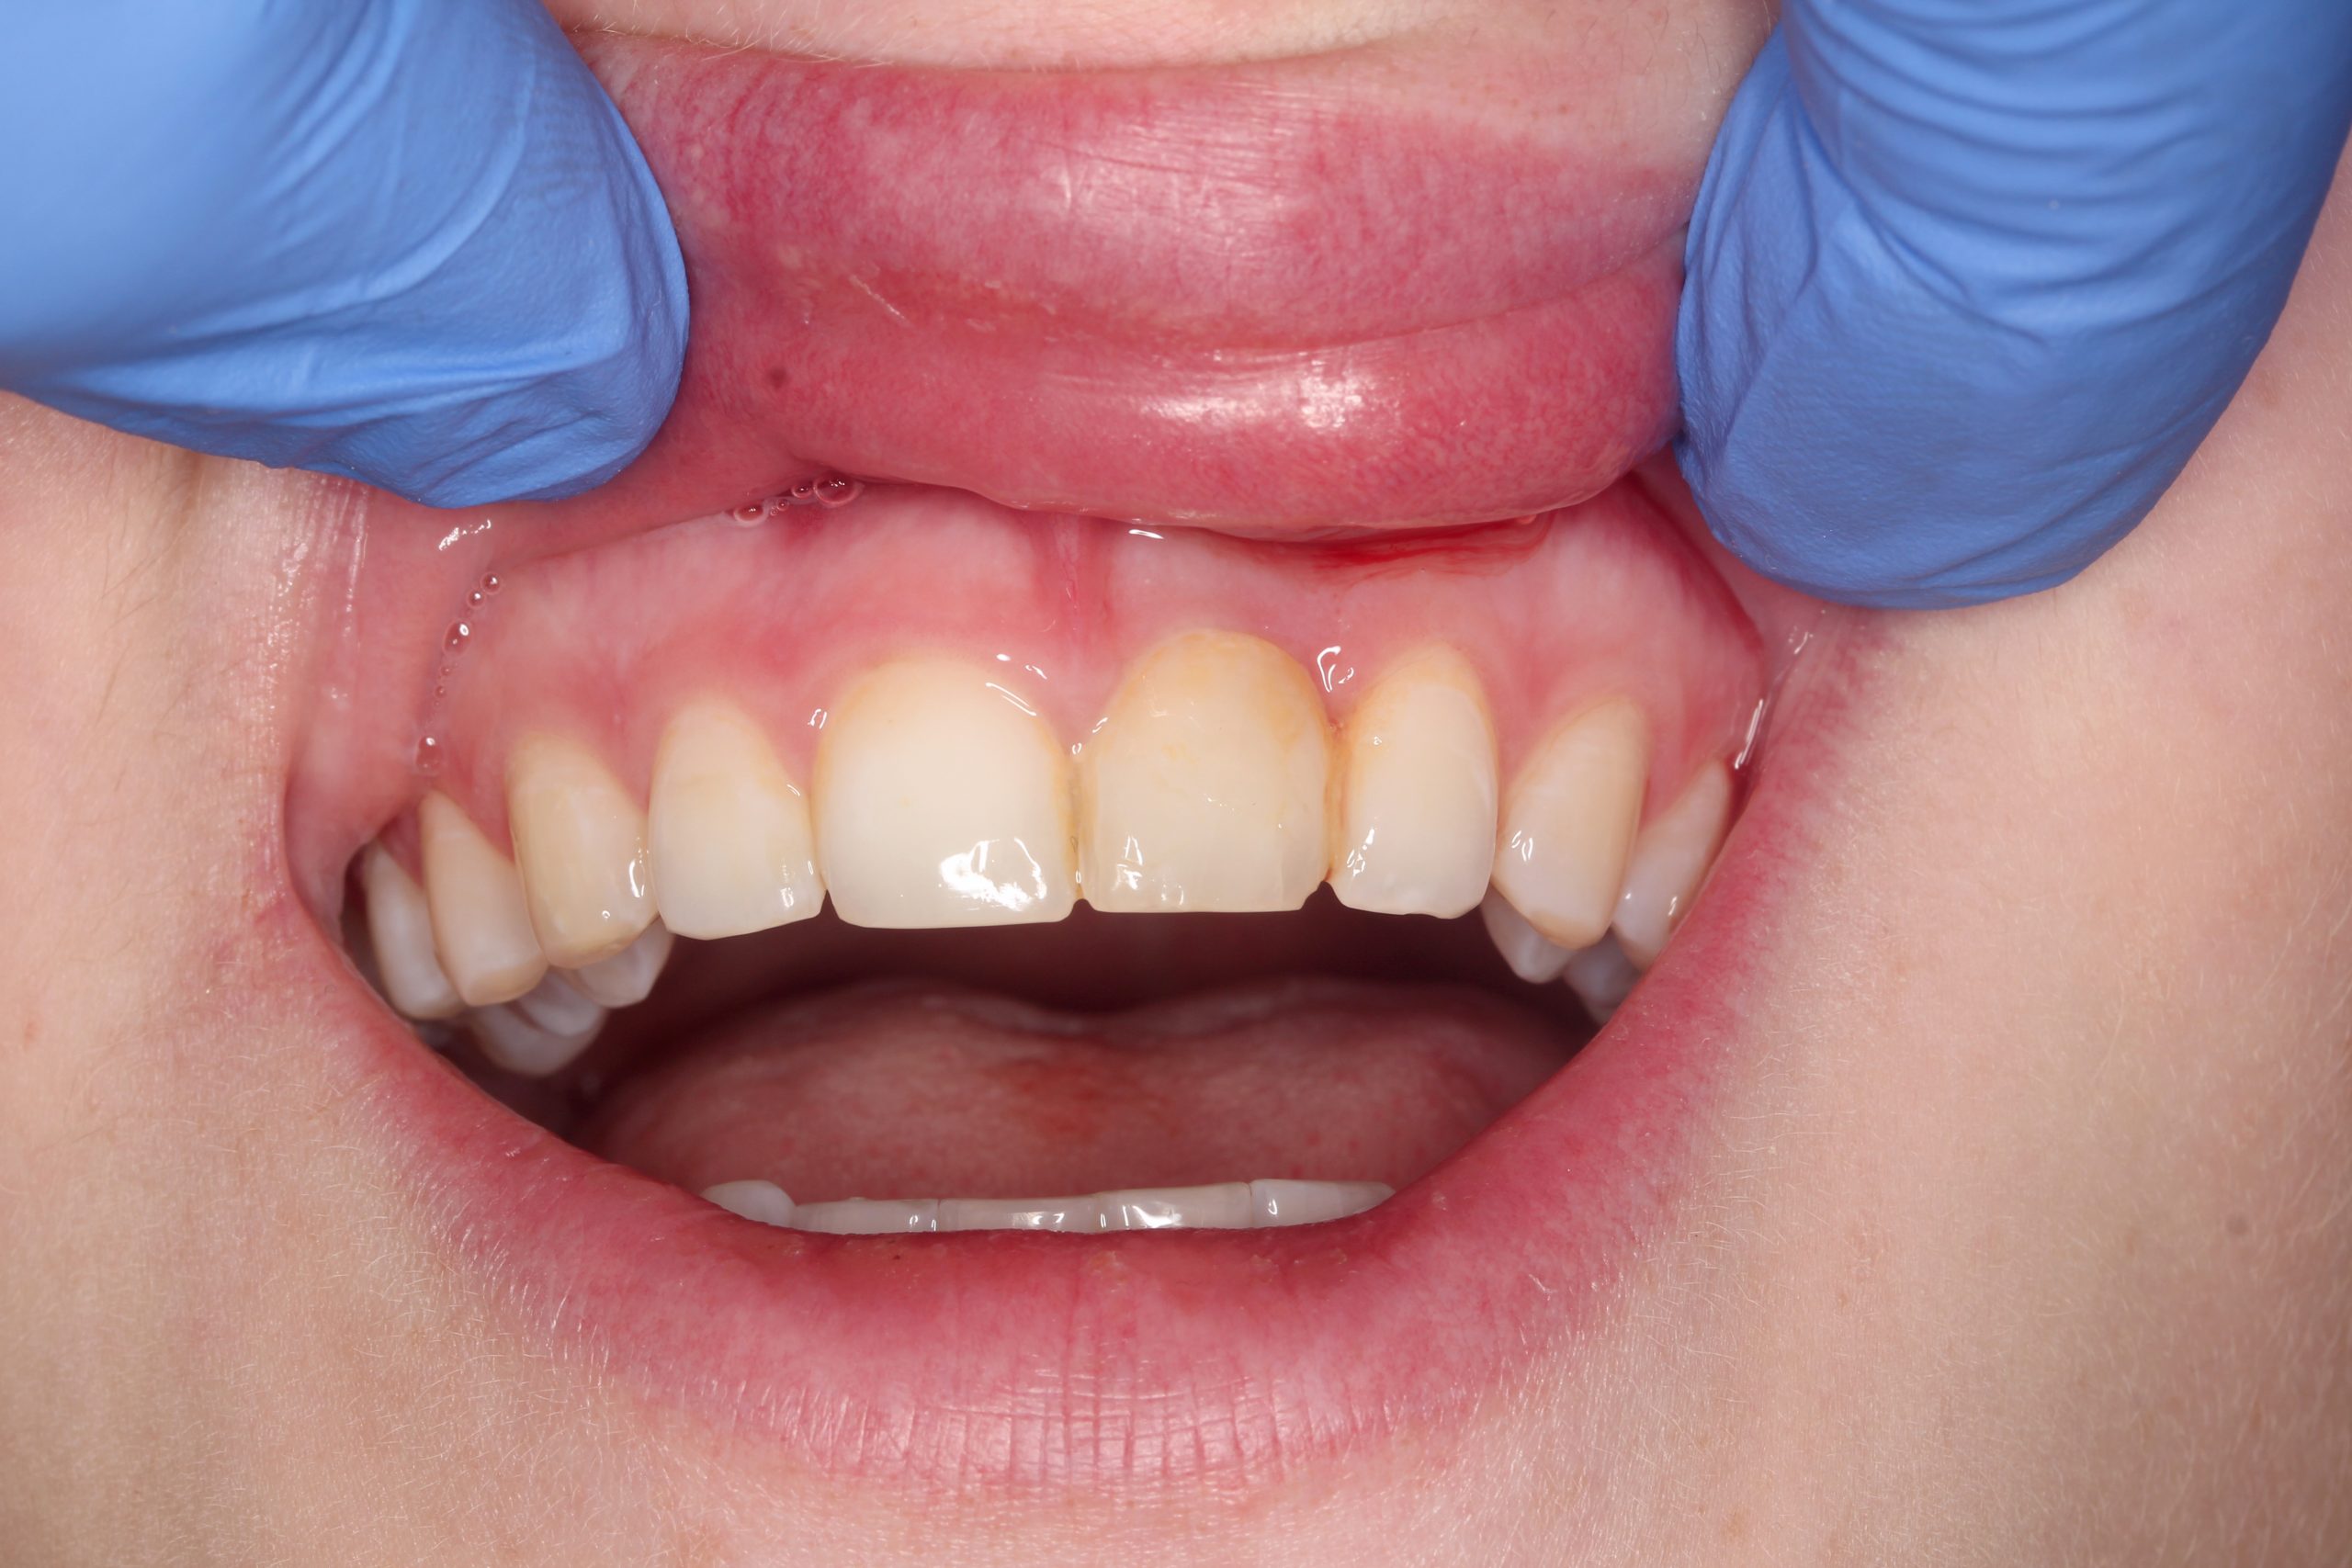

No problems occurred at the one-month follow-up. The temporary prosthesis was integrated into the surrounding tissue and the esthetics of the soft tissue were preserved.

Four months after implant placement and immediate loading, the temporary crown was removed. An all-ceramic crown was fabricated in the laboratory.

The patient‘s smile at the recall after three years. Minimally invasive surgical procedures and preservation of the surrounding tissue made it possible to achieve the best possible esthetic and functional result.